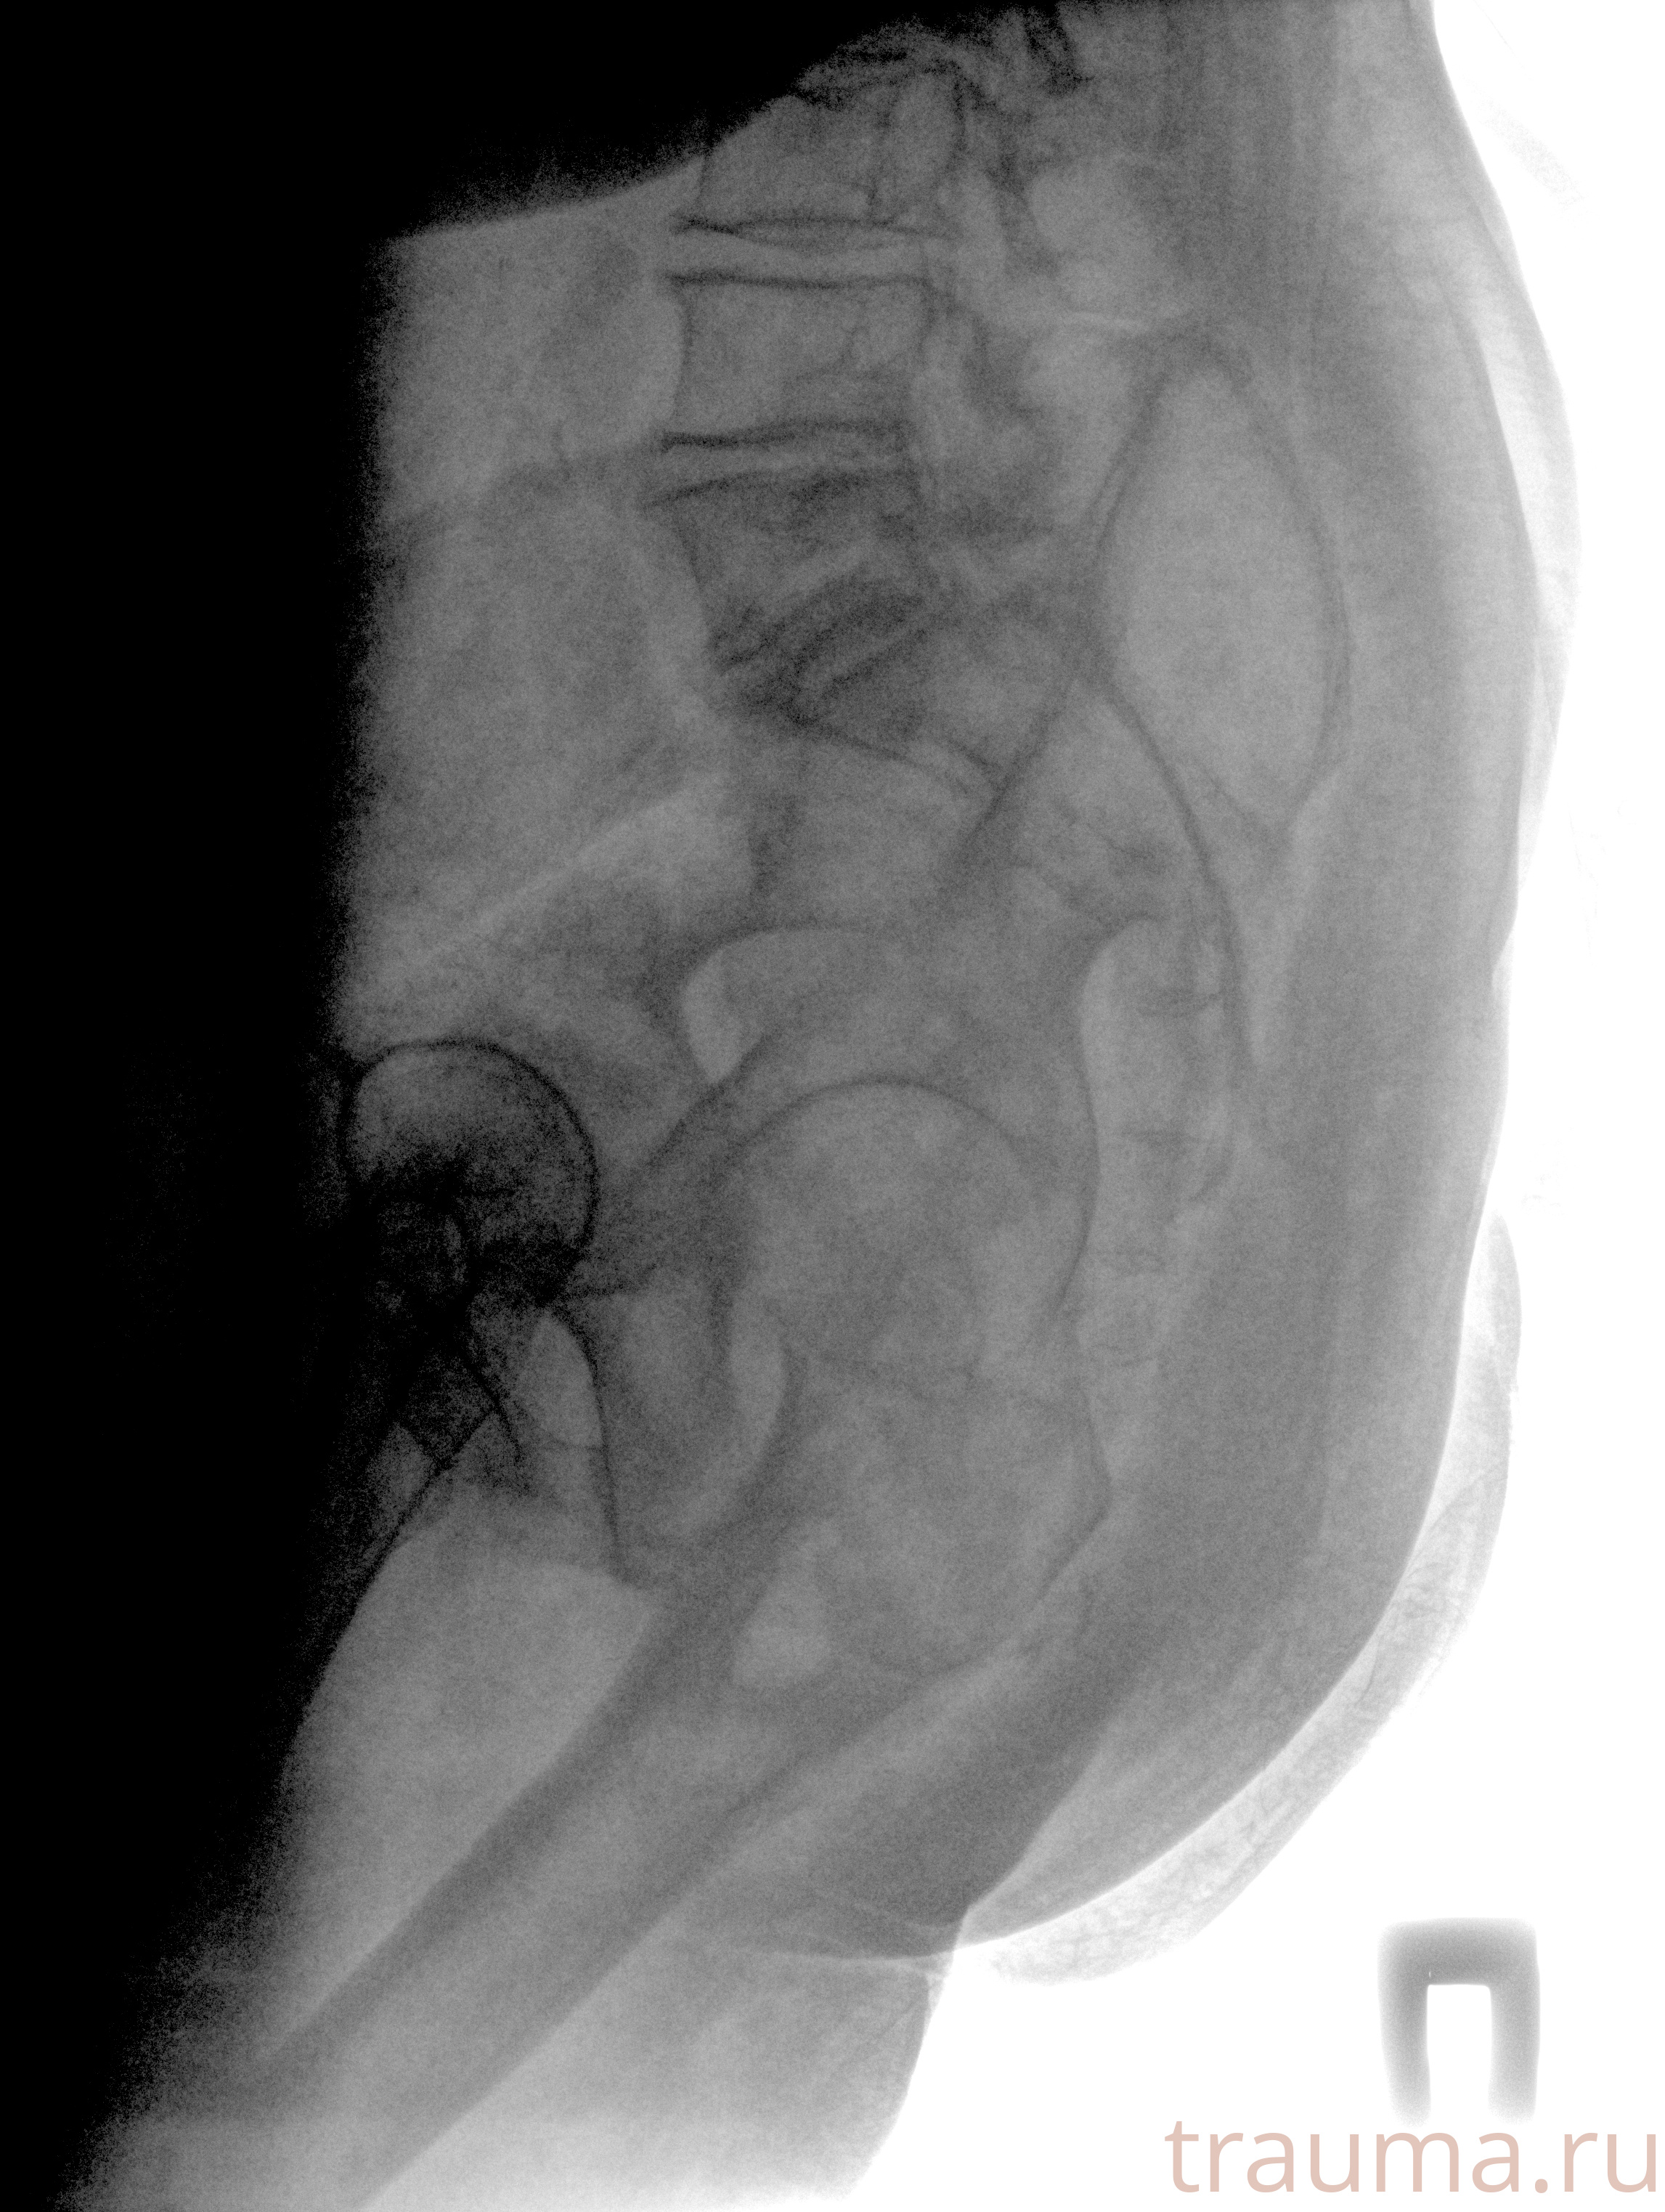

Рентгенограммы

Рентген на дому: по вашему адресу приезжает врач-рентгенолог, травматолог-ортопед с мобильным рентгеновским аппаратом, проводит диагностику травмы или заболевания, делает необходимые рентгенограммы, дает рекомендации по дальнейшему лечению. Получить качественные снимки в домашних условиях возможно благодаря уникальной методике, разработанной МосРентген Центром для института  Склифосовского

при переломе шейки бедра и пневмонии от компании МосРентген Центр - партнера Института имени Склифосовского